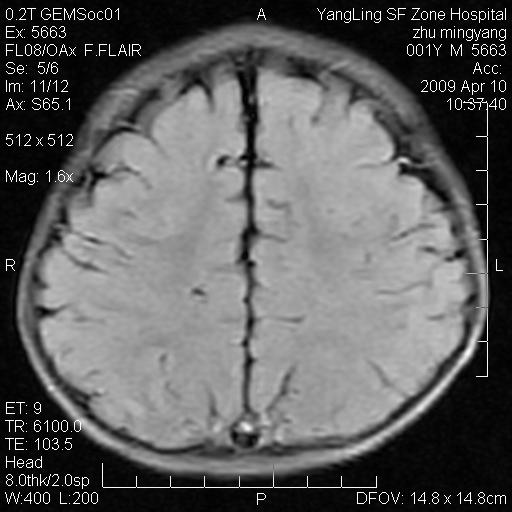

患者:1岁半,两天前外伤收住我院,ct检查小脑占位

考虑星形细胞瘤,建议增强

髓母细胞瘤或血管母细胞瘤,增强后可以鉴别;影像资料见 <。鱼博浪老师的《中枢神经系统ct与mr鉴别诊断》 小脑部肿瘤章节。

髓母细胞瘤或血管母细胞瘤!支持!

支持考虑髓母细胞瘤

考虑----髓母细胞瘤可能性大

考虑髓母细胞瘤或室管膜瘤。

支持髓母细胞瘤。

考虑髓母细胞瘤。

考虑髓母细胞瘤或星形细胞瘤

考虑髓母细胞瘤.

考虑髓母细胞瘤可能性大。

小脑肿瘤.考虑髓母细胞瘤可能.

就病灶部位及临床资料首先考虑髓母.